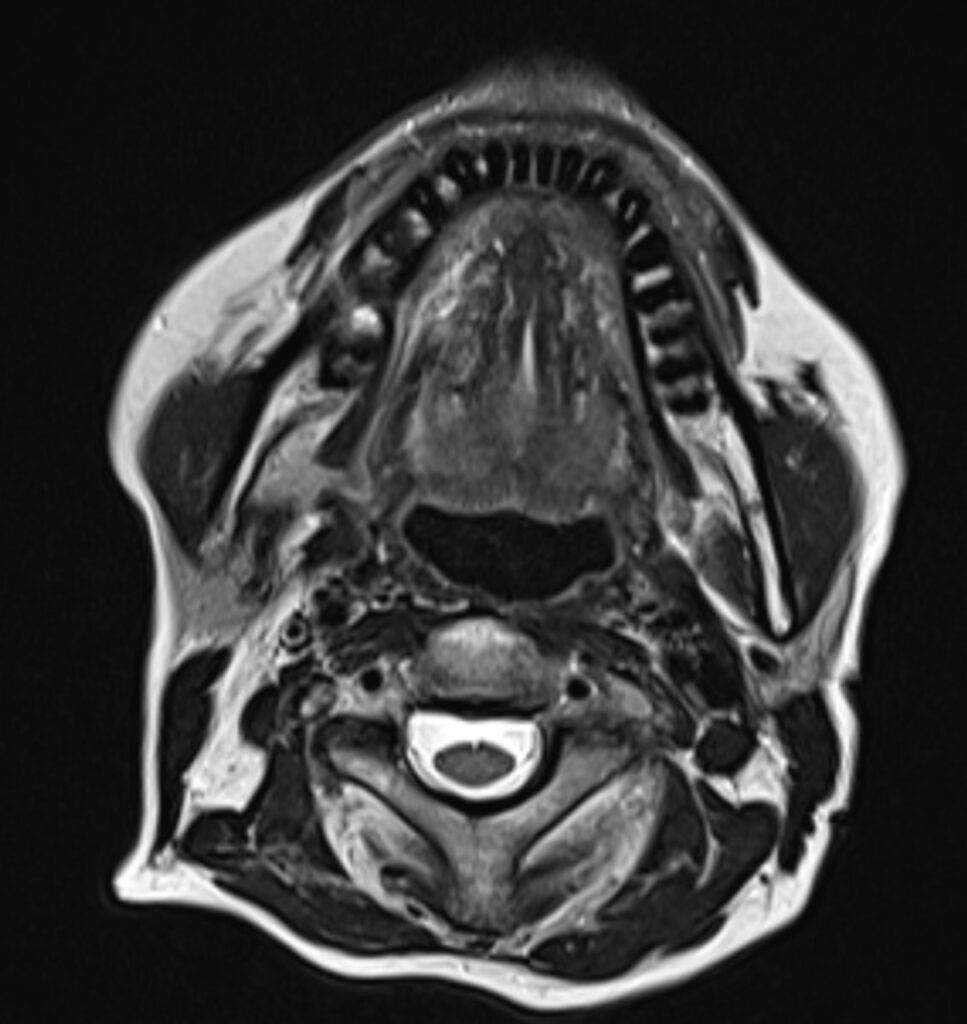

„MRT Kopf“ bezieht sich allgemein auf die Untersuchung des gesamten Kopfbereichs, einschließlich Gehirn, Schädel und umliegender Strukturen. „MRT Schädel“ sowie „MRT Gehirn“ beziehen sich auf dieselbe Untersuchung. Unterschieden wird im untersuchenden Bereich: Gehirn, Schädelknochen, Nase und Nasennebenhöhlen, Ohr oder Kiefer.

Eine MRT des Schädels wird verwendet, um Knochenanomalien, Frakturen, Entzündungen und bestimmte Krebserkrankungen zu diagnostizieren. Es ist besonders nützlich für die Untersuchung von Schädelknochen und deren Strukturen.